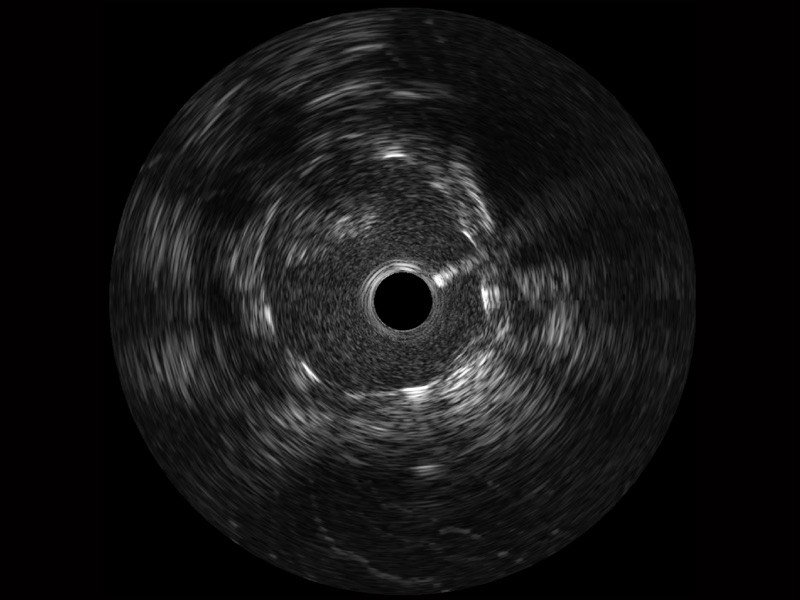

美狮贵宾会官网宽频IVUS图像

对比传统IVUS导管成像,美狮贵宾会官网宽频IVUS图像的近场支架梁显影更细腻,远场中膜外血管仍清晰可辨,兼顾远中近,兼顾分辨力与穿透深度